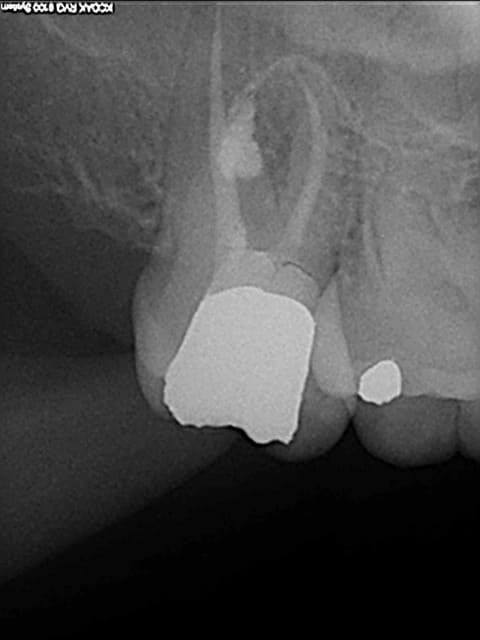

traitement endo réalisé en 2002 sur une 17 suite à pulpite liée à une carie sous un amalgame.

constatation d'un problème à la radio post-op que j'ai pris pour un resorption interne.

Je m'apercçois que ce que je croyais bêtement être une résorption est en fait une perfo et que le canal dv n'est toujours pas nettoyé et obturé.

Je nettoye et obture la perfo au MTA.